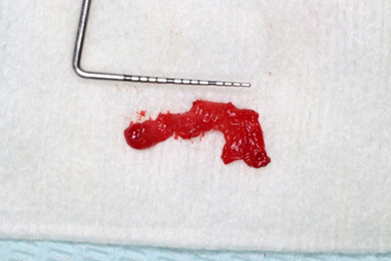

Recurrence is rare, occurring in 0-11% of cases, according to reports. Following surgery, full reconstruction of the bones within the bony defect is expected (8). The intra-oral assessment showed diffuse non-tender isolated swelling in the anterior mid-palatal region (Figure 13). Radiographically, it presents as a well-defined oval or round radiolucency in the maxillary anterior tooth region (Figure 14).

The treatment is done by complete enucleation of the cyst via palatal approach under local anesthesia. Palatal incision was performed and detachment of palatal mucosa in the region between the right and left canines approximately. Dissection was performed between the cystic capsule and the adherent mucosa, followed by cyst enucleation and cleaning of the cavity. The flap was sutured with 3/0 silk.

Figure 16: Size of the cyst.